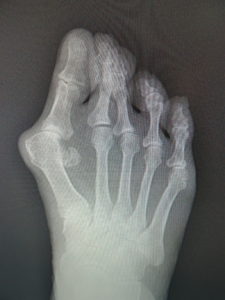

手術前 手術後4年

私は、ミッチェル変法ないしハモンド変法を行います(図6,7)。前日入院、腰椎麻酔(当日のみ臥床となります。)で一時間ほどの手術です。中足骨で骨切りを行い、長さも調節(多くはエジプト型足なので幾分短縮します。)しながら向きを矯正し、骨切り部をワイヤーで固定します。母趾内転筋の切離や、母趾外転筋の移行を検討します。中足骨頭部の種子骨を、正しい位置に戻して縫合します。術後は念のため、3週間ほど短いソックス型のギプスを装着しますが、術翌日から歩行訓練などの理学療法を行います。1ヵ月半ほどで骨癒合します。骨癒合が得られなかった症例はありません。2~3か月で普通に靴が履けます。入院期間は相談して決めればよいのですが、最短なら抜糸まで10日間、或いはギプス固定期間の3週間などが目安となります。

(図6)

手術前 手術後

(図7)

真田理事長による手術の様子。外反母趾|症例 (左から 手術前、手術後、ワイヤ抜去後)